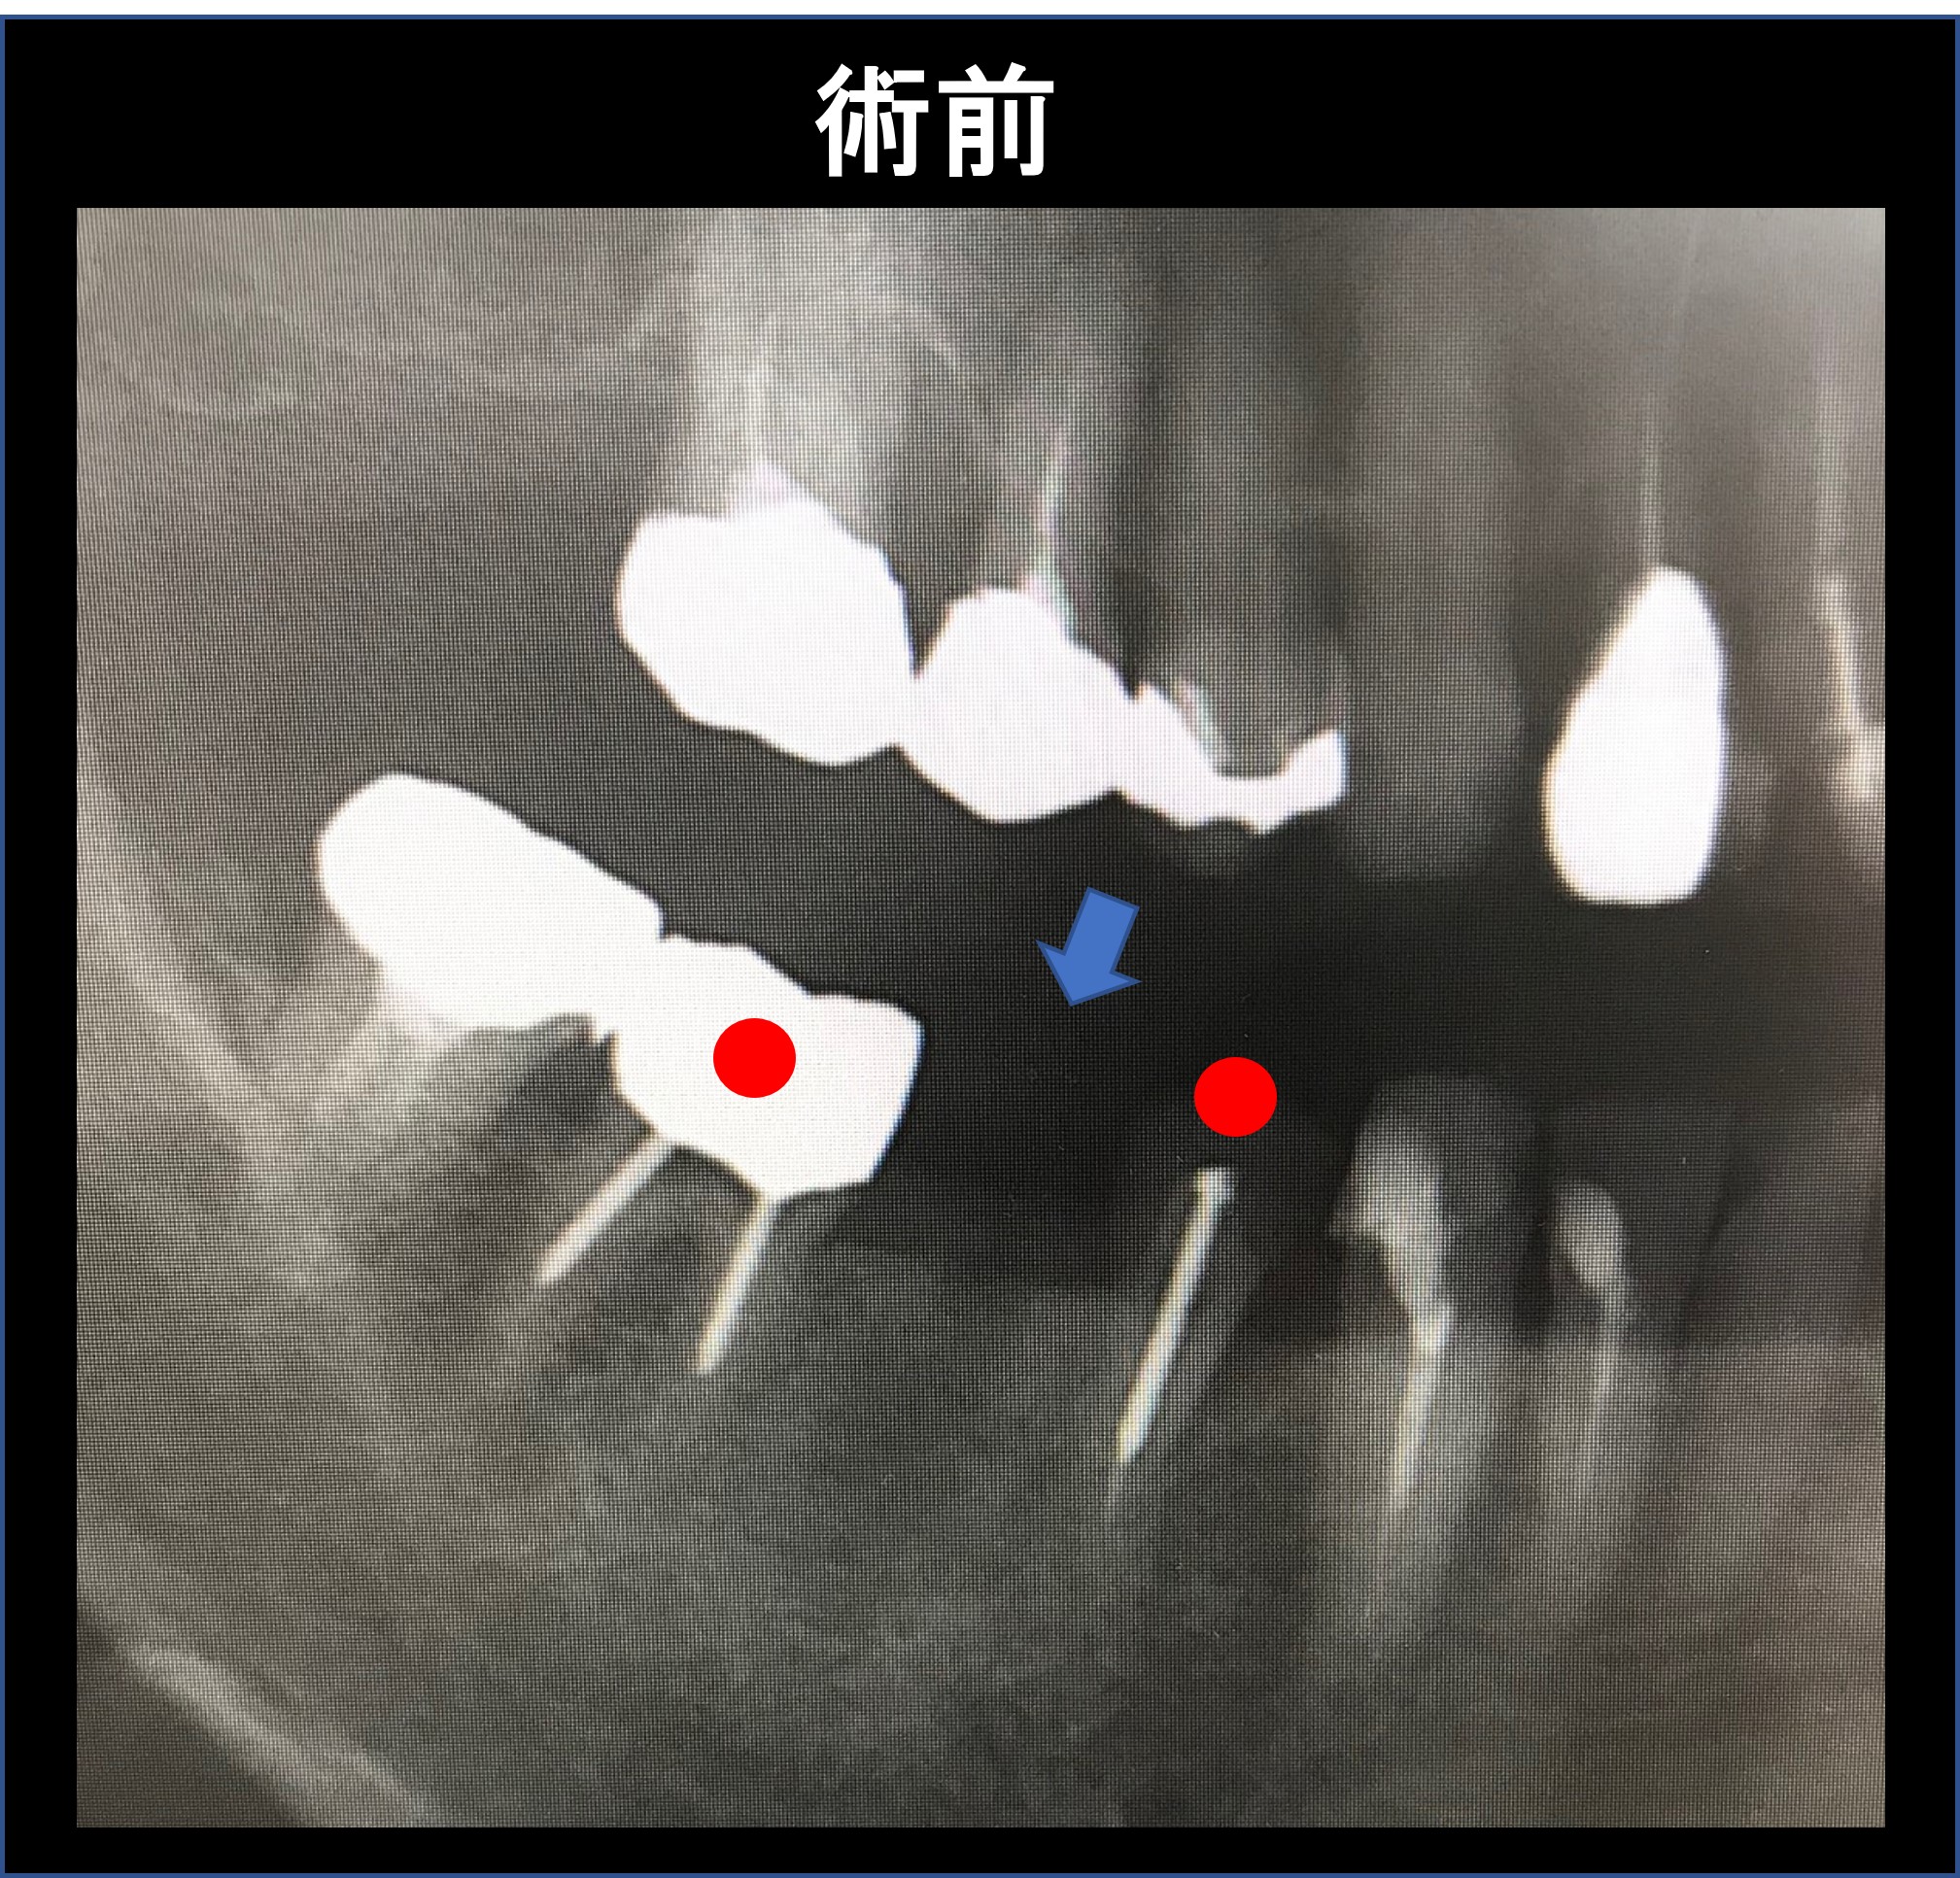

渡辺歯科医院HOME > 渡辺歯科医院Blog > インプラント 歯周病専門医 渡辺歯科医院 小矢部市 砺波市 南砺市 富山県